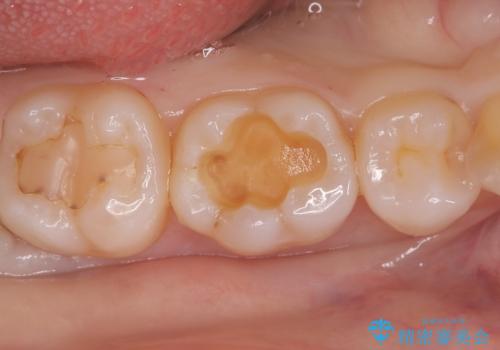

- 銀歯を外したいことを主訴に来院されました。

銀歯を丁寧に取り除き、形態を整えた上で、セラミックインレーで修復しました。